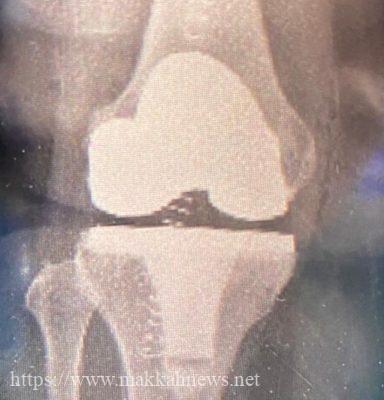

في إنجاز غير مسبوق على مستوى المستشفيات الطرفية نجح مستشفى الملك خالد في محافظة المجمعة في إجراء أول عملية إستبدال ركبة صناعية لسيدة كانت تعاني من مشكلة في الركبة وصعوبة في الحركة حيث إتضح بعد عمل الفحوصات والأشعة حاجتها لإجراء العملية وقد تمكنت بفضل الله من المشي بعد العملية مباشرة وذلك بإشراف الفريق الجراحي وفريق العلاج الطبيعي، كما تم التأكد من سلامتها وعمل الفحوصات اللازمة والتأكد من السيطرة على الآلام وإعتمادها على نفسها في الحركة وأستطاعت الخروج بعد أقل ٤٨ ساعة من إجراء العملية وهي بصحة جيدة ولله الحمد

تجدر الإشارة أن مستشفى الملك خالد في المجمعة قام بتأسيس برنامج جراحة إستبدال المفاصل الصناعية لمرضى خشونة مفصل الركبة وذلك نظراً للحاجة الماسة لمثل هذه الجراحات بسبب طول فترات الإنتظار في المستشفيات الرئيسة وتكبد عناء السفر بالنسبة للمرضى لإجراء هذه العمليات

ويحتوي البرنامج على أحدث البروتوكلات في عمليات مفصل الركبة وإستخدم أحدث الطرق العلمية لإجراء العملية بواسطة الجراح المختص وذلك بإستخدام أكفأ أنواع المفاصل الصناعية كما يتميز البرنامج بالإعتماد على التأهيل السريع و حركة المريض مباشرة بعد العملية وتقليل مدة التنويم إلى أقل من ٤٨ ساعة وضمان الحرص على سلامة المريض وإعتماد المريض على نفسه في الحركة قبل الخروج من المستشفى ويعتبر هذا البرنامج من أحدث البرامج لمثل هذه العمليات حيث يعتمد العمل على الفريق الواحد من أطباء التخدير و أخصائيي العمليات وفريق العلاج الطبيعي والتمريض والصيدلة